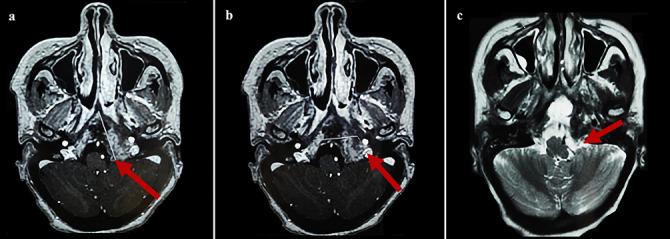

Plasmacytoma is a rare plasma cell neoplasm. Whether solitary or associated with multiple myeloma (MM), it rarely involves the skull base, particularly the sphenoid bone. We present a unique case of sphenoid bone plasmacytoma secondary to MM, highlighting diagnostic and therapeutic challenges. A 56-year-old female presented with headaches, vomiting, epistaxis, and cranial nerve deficits. Cerebral imaging revealed a 65-mm tumor infiltrating the sphenoid bone and adjacent structures. Subtotal resection was performed using an endoscopic nasal approach. Histopathology revealed plasmacytoma, and diagnostic workup confirmed MM. By the end of biological exploration, relapse of the sphenoid plasmacytoma was observed, and the patient was successfully treated with radiotherapy, immunochemotherapy, and autologous stem cell transplantation. After 18-month follow-up, sustained complete remission was confirmed. Although rare, the diagnosis of plasmacytoma should be considered in cases of skull base tumors. This localization is highly predictive of MM, warranting comprehensive investigations to initiate prompt and adequate management.

浆细胞瘤是一种罕见的浆细胞肿瘤。无论是孤立性还是与多发性骨髓瘤(MM)相关,它很少累及颅底,尤其是蝶骨。我们报告一例继发于MM的蝶骨浆细胞瘤的独特病例,突出诊断和治疗挑战。一名56岁女性出现头痛、呕吐、鼻出血和颅神经功能缺损。脑部影像学检查发现一个65毫米的肿瘤浸润蝶骨及相邻结构。采用鼻内镜入路进行了次全切除。组织病理学显示为浆细胞瘤,诊断检查证实为MM。在生物学检查结束时,观察到蝶骨浆细胞瘤复发,患者接受放疗、免疫化疗和自体干细胞移植后成功治愈。经过18个月的随访,确认持续完全缓解。尽管罕见,但在颅底肿瘤病例中应考虑浆细胞瘤的诊断。这种定位高度提示MM,需要进行全面检查以便及时进行充分治疗。